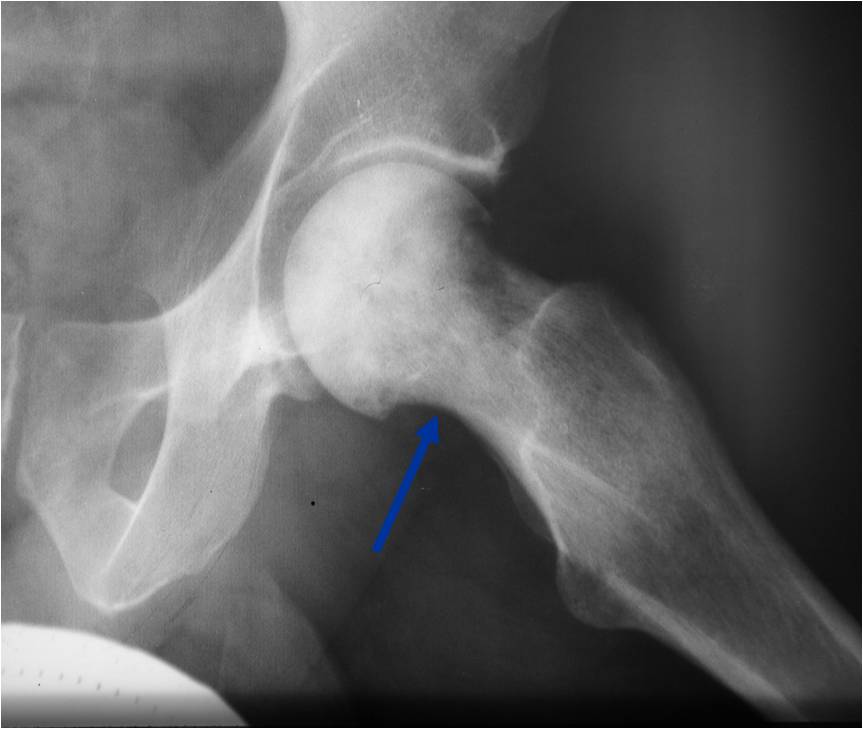

Permeative Lesion of Proximal Tibia with Pathological Fracture

Permeative/Motheaten Lesion with Pathologic Fracture

- Pathologic Fracture (22%)